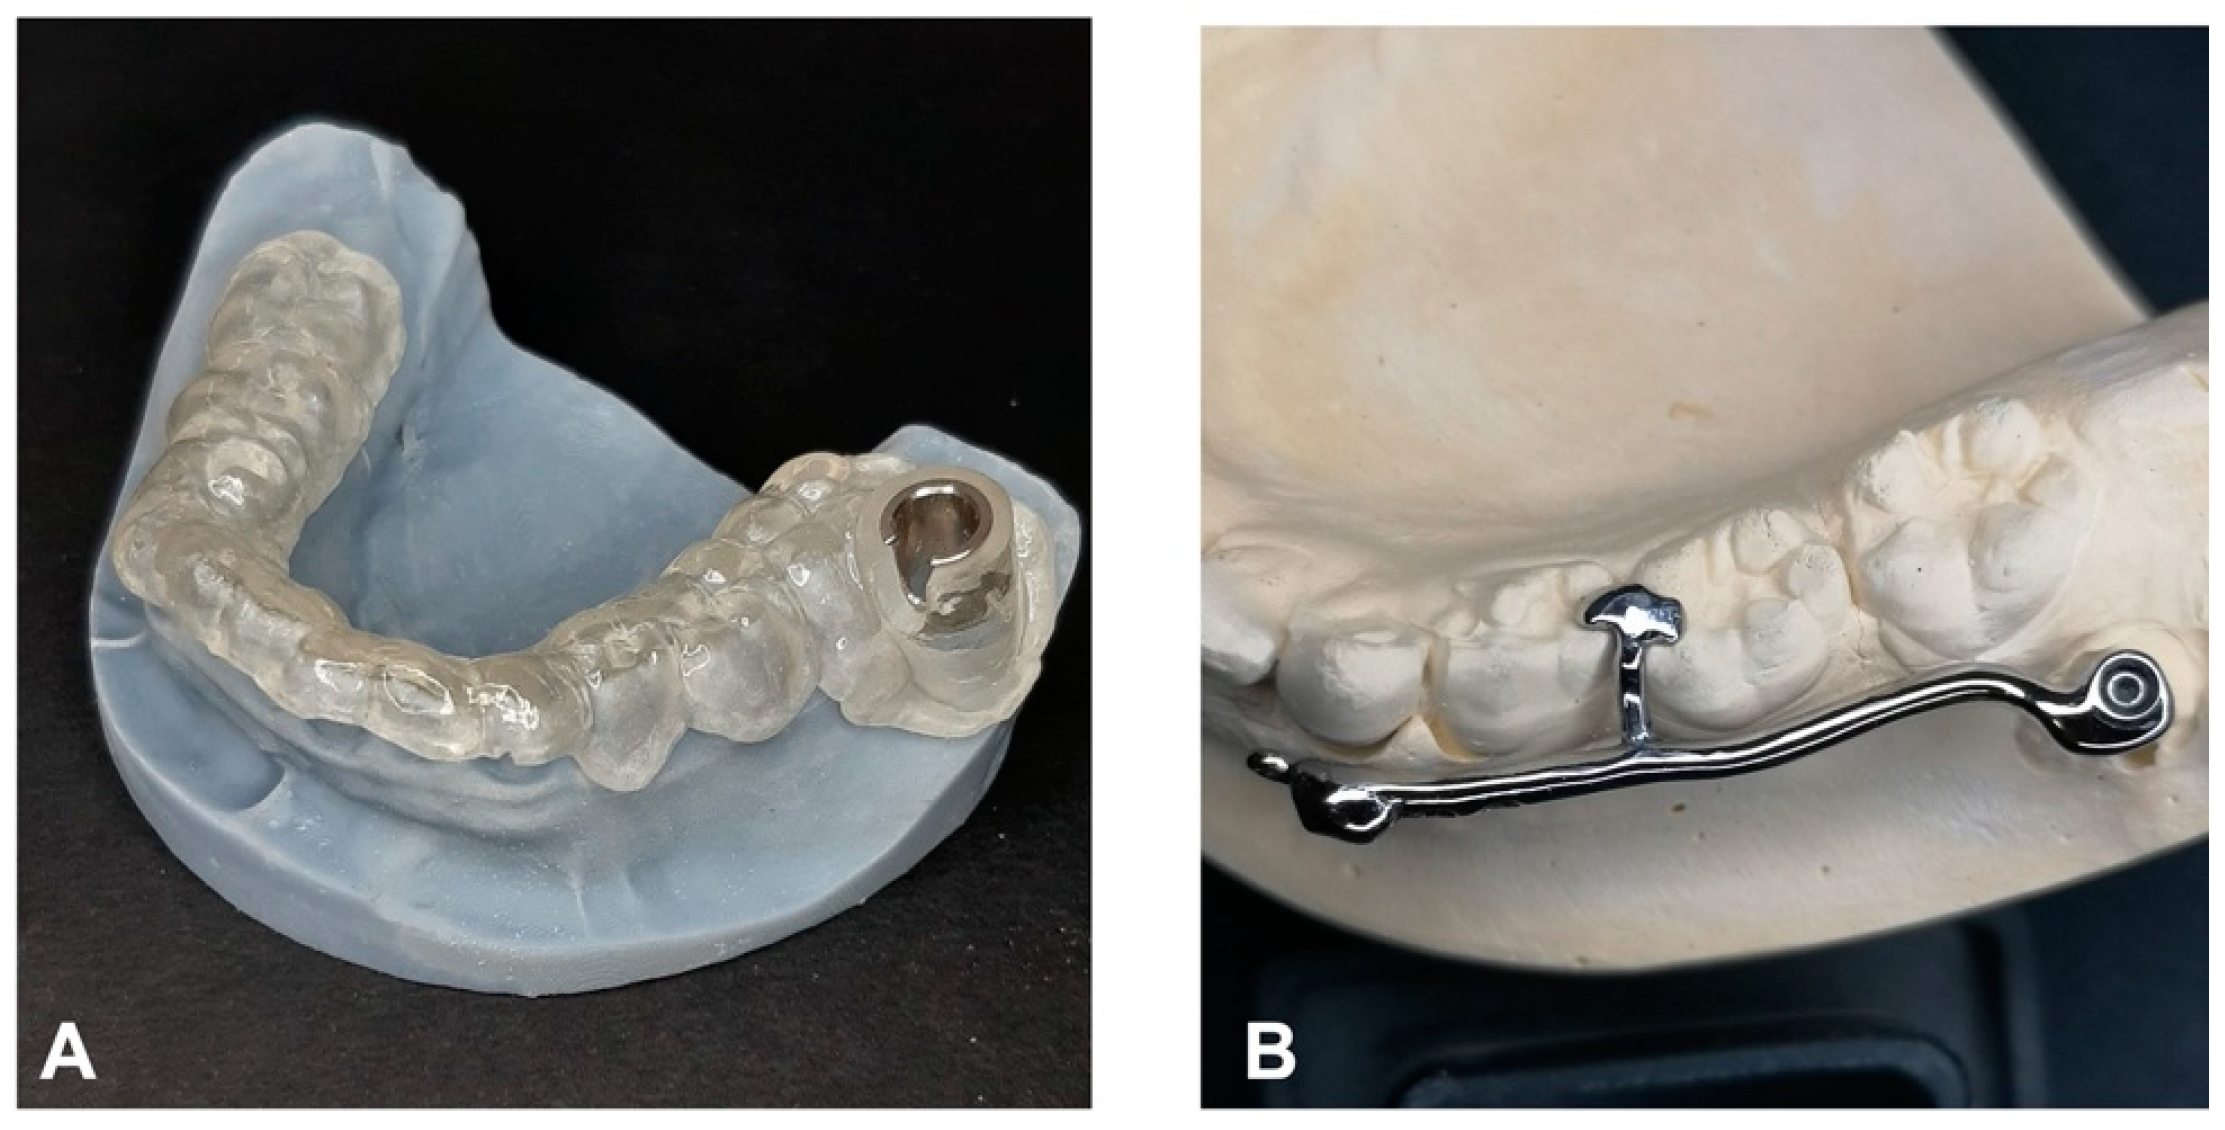

The procedure and potential risks associated with canine disimpaction, with particular emphasis on the risk of root resorption to adjacent elements, were fully explained to the subject and parents and signed informed consent for the publication of images and data was obtained. The disimpaction treatment consisted of a surgical phase of exposure of the impacted canine, with the possible removal of eruptive obstructions, and an orthodontic traction phase performed with a custom-made skeletal and dental anchorage device. The miniscrew insertion sites were planned on 3D images generated by merging CBCT and digital dental model images. The TADmatch 3D module of the Onyxceph3™ software (Image Instruments, Chemnitz, Germany) was used for the computer-guided planning of screw insertion using a surgical guide (Figure 5). A CAD/CAM digital workflow was performed to design the surgical guide and the skeletal anchoring disimpaction device using the Ortho Apps 3D module of the Onyxceph3™ software 3.2.180 Build 492–K2 (Image Instruments, Chemnitz, Germany) (Figure 6). The surgical guides were fabricated using TruPrint 1000 (TRUMPF Homberger S.r.l, Buccinasco, Italy) and the disimpaction device by laser melting technology with cobalt chrome metal powder (Stratasys OrhoDesktop; Stratasys, Rehovot, Israel) (Figure 7).

The length and diameter of the self-drilling titanium miniscrews used (BENEfit, PSM medical solutions, Tuttlingen, Germany) were predetermined during the planning phase based on bone anatomy (length: 13 mm; diameter: 2.3 mm). The miniscrew was inserted in the buccal shelf of the mandible, at the level of the mandibular first molar, on the left side; the appliance extended buccally from the miniscrew until the crown of the deciduous canine with a terminal hook and progressively distal holes for the insertion of orthodontic traction. Given the distance of the miniscrew from the disimpaction site, the device was designed to be very rigid with steel alloy with the rest cemented to the dental elements, which also had the function of preventing the device from rotating given that miniscrews are not equipped with effective anti-rotation devices.

Figure 7. Customized surgical template (A) and disimpaction device with miniscrews (B) on the 3D-printed digital mandible model.